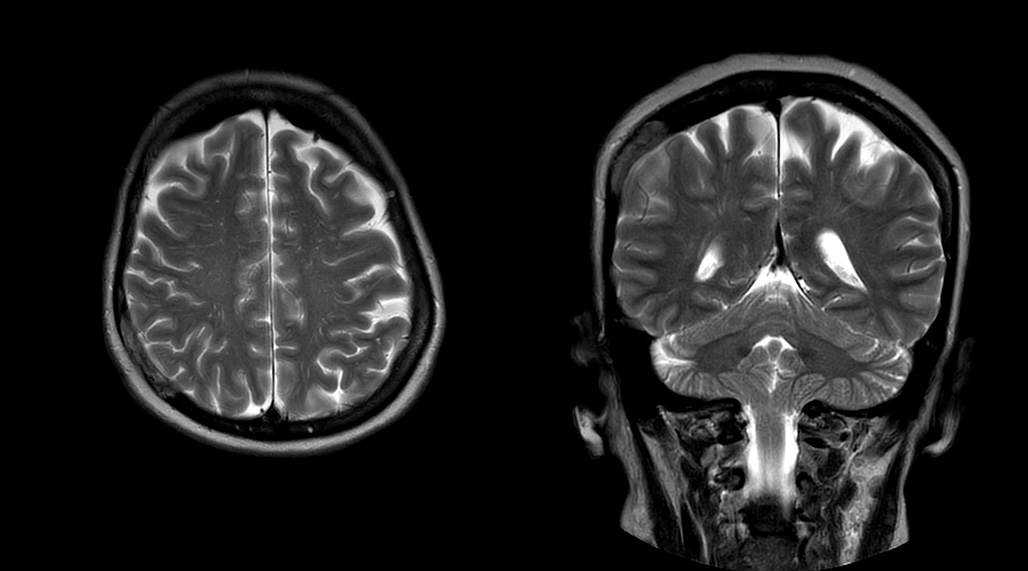

DMG recognizes MultiVane XD motion compensation is another Philips technique that contributes to image quality and scan efficiency. “We run MultiVane XD for motion-free imaging on almost all our T2-weighted brain scans, just to reduce any repeats we might get. We know our non-contrast brain scans are going to take 20 minutes almost every time,” Mr. Duffy says.

“Using MultiVane XD still allows us to turn on dS SENSE, which significantly cuts scan time compared to what we were doing before,” he adds. “We went from a 2.5 or 3-minute scan to a 1.5-minute scan with no loss in image quality. So, it not only reduces the motion, but also reduces scan time. That gives us a little bit of extra time to speak to our patients and explain the exam a little more.”